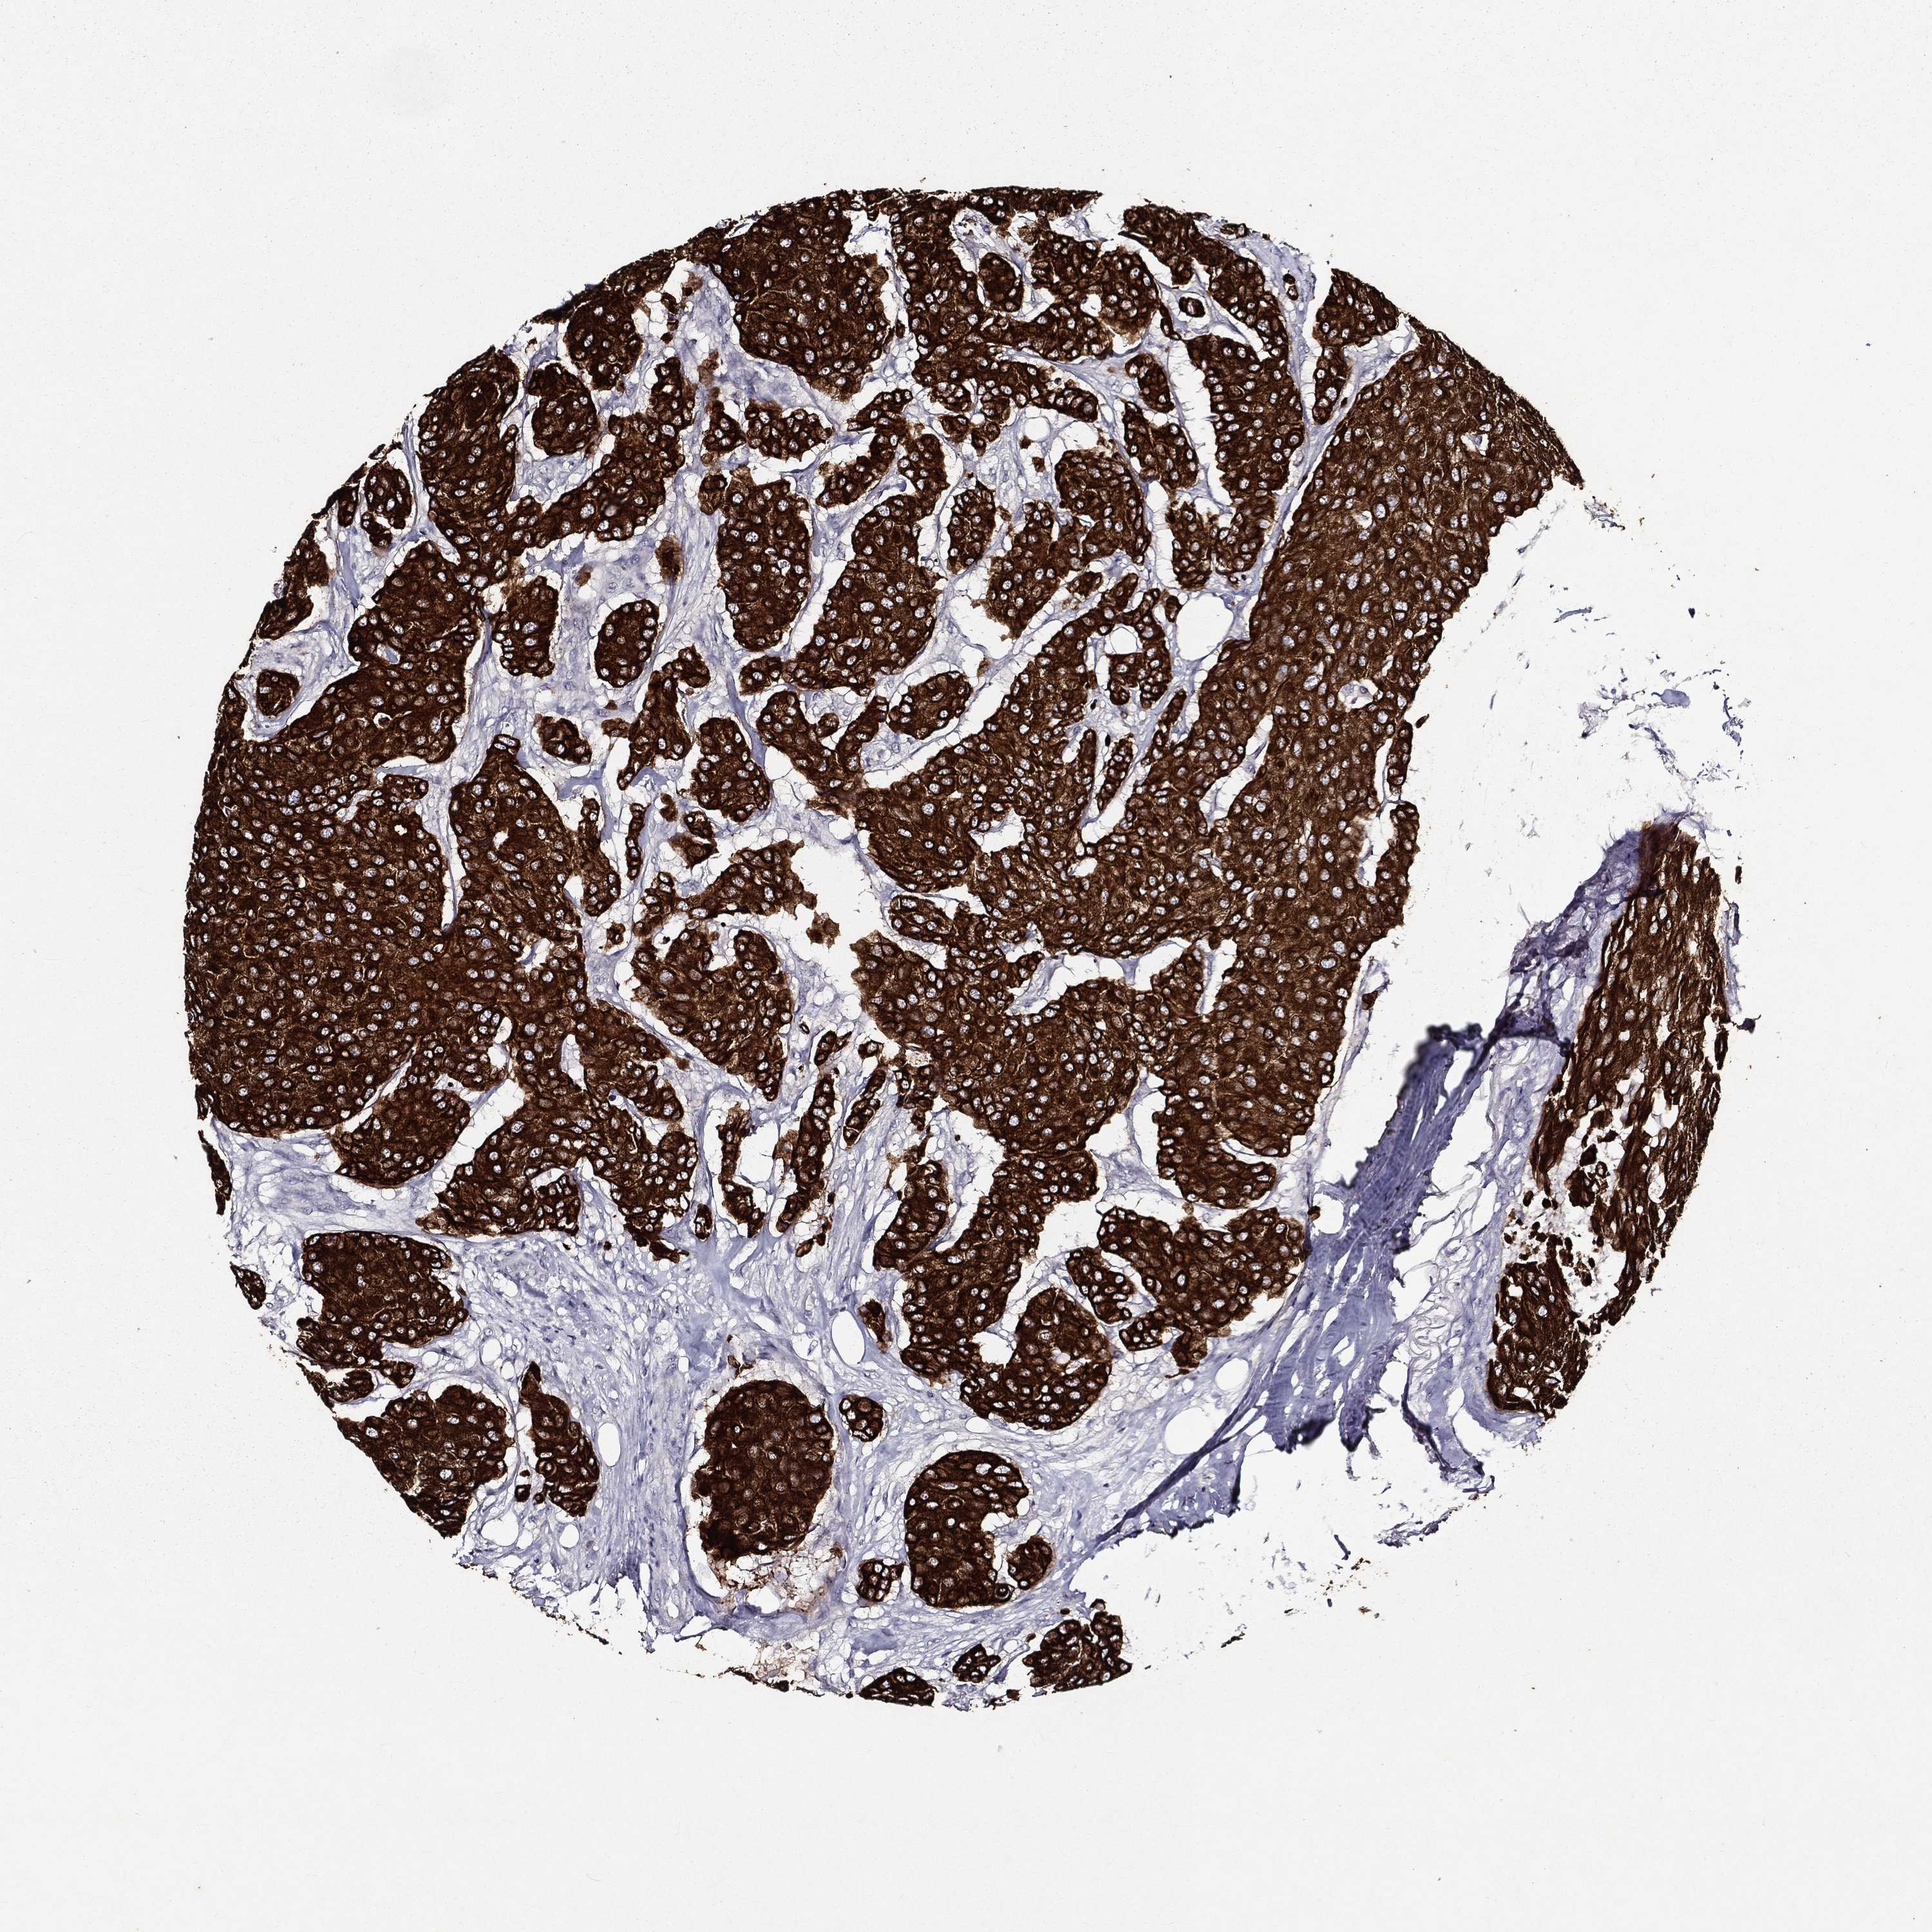

KRT7

CANCER BREAST CANCER Show tissue menu

Breast cancer

Human cancer

Breast invasive carcinoma